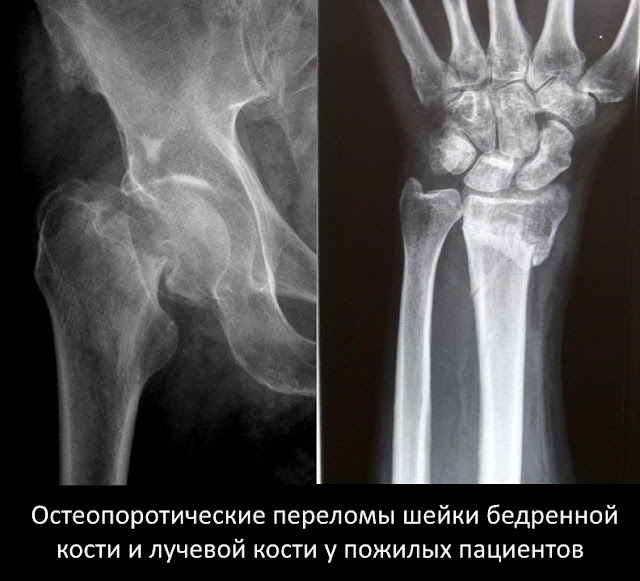

Чаще всего наступают переломы лучевой кости в области лучезапястного сустава, переломы шейки бедренной кости и позвонков. Первые два вида переломов наступают остро, как обычный перелом. Перелом лучевой кости худо-бедно срастается, а перелом шейки бедра – нет. Оперировать таких пациентов в ЦРБ никто не берется из-за сопутствующих болезней. Старики становятся лежачими больными и погибают в течение года от осложнений малоподвижного образа жизни.